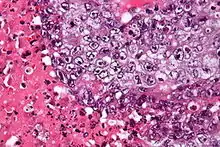

Micrograph of an embryonal carcinoma showing its typical features – prominent nucleoli, marked nuclear atypia, necrosis, and nuclear overlap. H&E stain.

The microscopic features include: indistinct cell borders, mitoses, a variable architecture (tubulopapillary, glandular, solid, embryoid bodies – ball of cells surrounded by empty space on three sides), nuclear overlap, and necrosis.